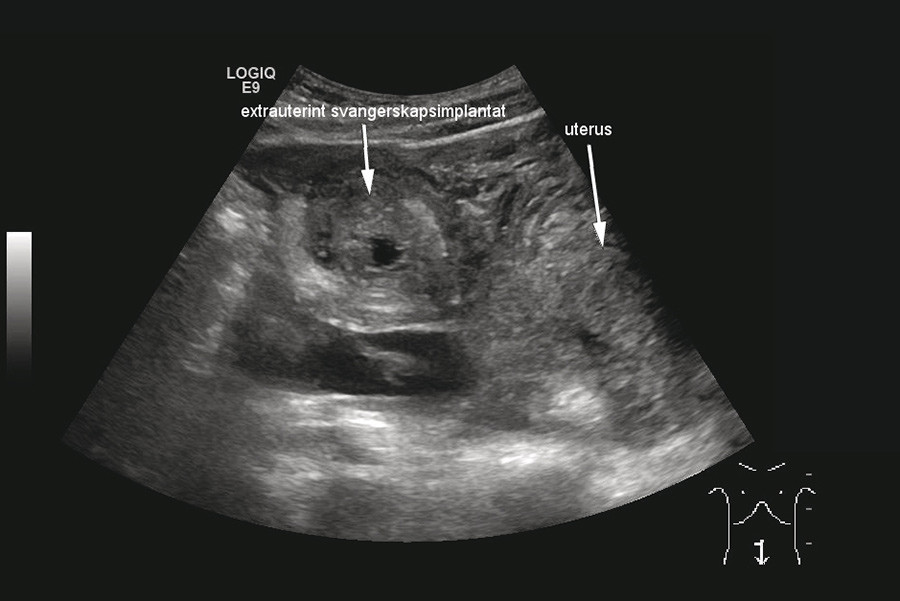

Blodprøver ved innkomst viste humant choriongonadotropin (HCG) i serum på 4 544 (0 – 4). Hemoglobin (Hb) var på 8,9 (11,7 – 15,3), og sank til 7,8 noen timer senere. I mellomtiden var det gitt vanlig intravenøs væskebehandling. Ultralyd abdomen viste «store mengder fri væske i buken med ekkomønster forenelig med blod» (fig 2) og «uregelmessig oppfylning på ca. 5 cm like kranialt for uterus, forenelig med ekstrauterin graviditet» (fig 3).